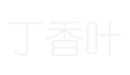

• Hiatal hernias

1. Thoracic esophagus

2. Thoracic cavity

3. Right crus

4. Left crus

5. Abdominal esophagus

6. Fundus of the stomach

Hiatal hernias cause most gastroesophageal reflux diseases (GERD).

• Type I hiatal hernias

• Stage 1

Sliding hiatal hernias occur when the abdominal esophagus migrates through the hiatus while the gastroesophageal junction (GEJ) and stomach remain below.

As the abdominal esophagus migrates, the EGV disappears due to the widening of the esophagogastric angle, and the LESE diminishes due to the loss of anatomical relationships and extrinsic pressures.